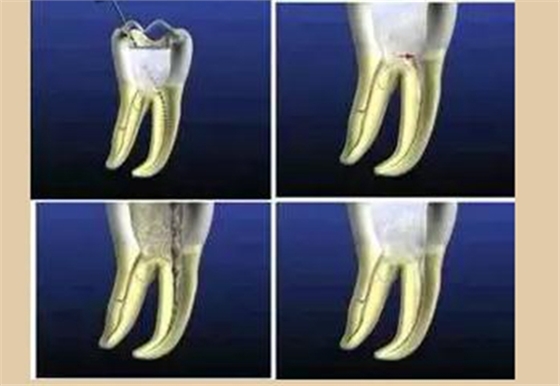

根管治療術(shù)是醫(yī)生用根管治療專(zhuān)用器械通過(guò)徹底去除感染的牙髓以及感染的牙本質(zhì)和毒性分解產(chǎn)物,經(jīng)過(guò)根管沖洗、消毒和嚴(yán)密填塞根管,隔絕細(xì)菌進(jìn)入根管再感染,防止根尖周病變的發(fā)生或促進(jìn)根尖周病的愈合。

一、開(kāi)髓去腐質(zhì)

根管治療開(kāi)髓前必須去凈腐質(zhì),然后換用另一根新的車(chē)針(裂鉆或金剛砂車(chē)針均可,但金剛砂車(chē)針開(kāi)髓震動(dòng)感少,開(kāi)髓穩(wěn))進(jìn)入髓腔,穿通髓腔后換高速球鉆揭頂,揭頂一定要全,以能看清整個(gè)髓室底為準(zhǔn),然后換用裂鉆或金剛砂車(chē)針修整髓壁。

根管預(yù)備是通過(guò)機(jī)械方式配合化學(xué)藥物去除、清理根管里面的污染物,使根管成為一定形態(tài),利于沖洗和充填。